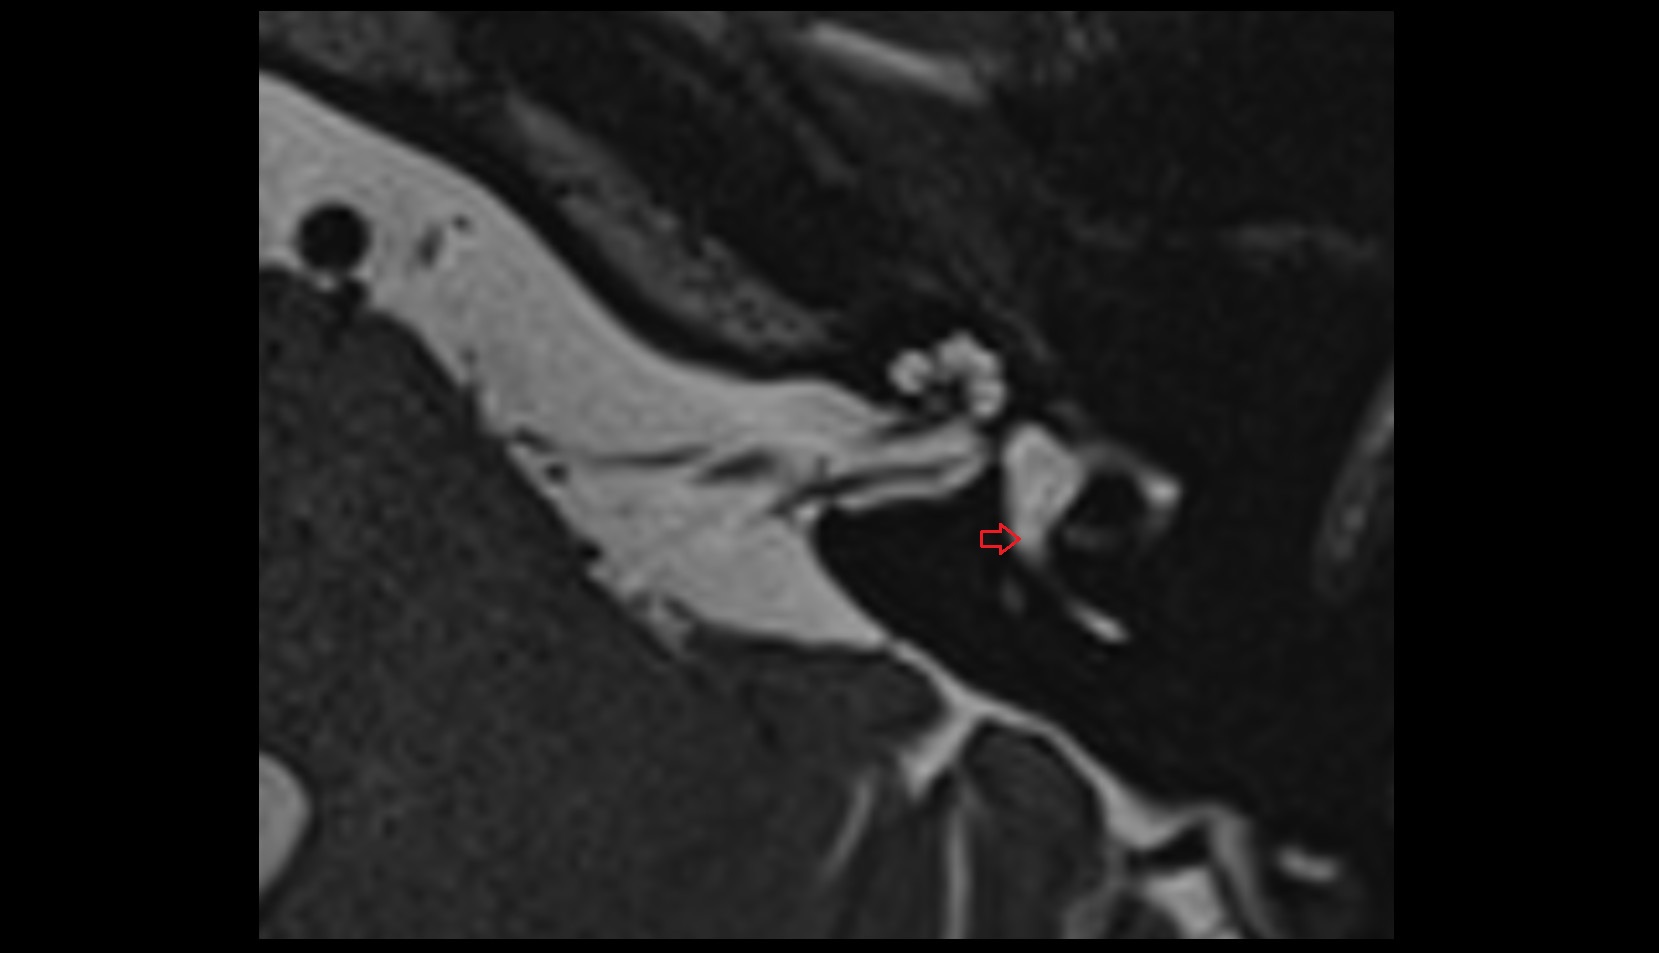

- Temporomandibular joint

- Articular disc of temporomandibular joint

- Articular eminence

- Mandibular condyle

- Mandibular fossa